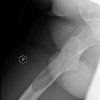

Retrospective case study 66 Male 1 year history of right thigh pain Attended physiotherapy. Given exercises for tight thigh muscle. No improvement. Consulted GP 10-12 months after physiotherapy as he developed problems with sit to stand. GP requested X-ray pelvis. X-ray report as follows. GP referral for x-ray mentions – “Injury right leg two [...] Read more